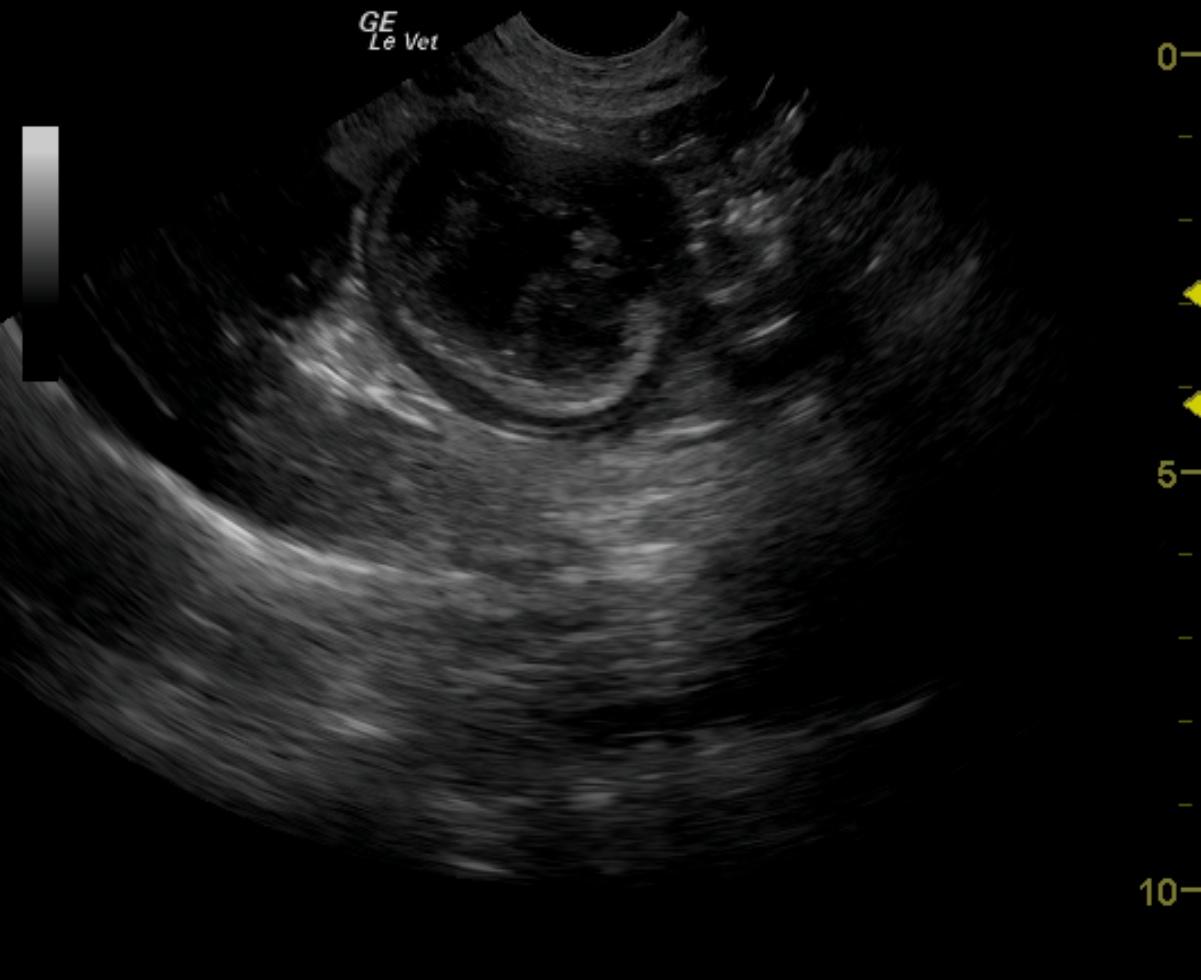

From members.sonopath.com

Intestinal stromal tumor in a 11 year old MN Brittany Spaniel dog Members Dog Gastrointestinal Stromal Tumor gastrointestinal stromal tumor (gist) is a malignant mesenchymal neoplasm described in humans, dogs, and. fifty canine gastrointestinal (gi) mesenchymal tumors were examined to determine the occurrence of leiomyomas. gastrointestinal stromal tumors (gists), leiomyomas, and leiomyosarcomas are common mesenchymal neoplasms in the. fifty canine gastrointestinal (gi) mesenchymal tumors were examined to determine the occurrence of leiomyomas. . Dog Gastrointestinal Stromal Tumor.

Intestinal stromal tumor in a 11 year old MN Brittany Spaniel dog Members Dog Gastrointestinal Stromal Tumor fifty canine gastrointestinal (gi) mesenchymal tumors were examined to determine the occurrence of leiomyomas. fifty canine gastrointestinal (gi) mesenchymal tumors were examined to determine the occurrence of leiomyomas. adenocarcinoma, leiomyosarcoma, and lymphoma are the most common canine intestinal tumors. gastrointestinal stromal tumor (gist) is a malignant mesenchymal neoplasm described in humans, dogs, and. in dogs,. Dog Gastrointestinal Stromal Tumor.